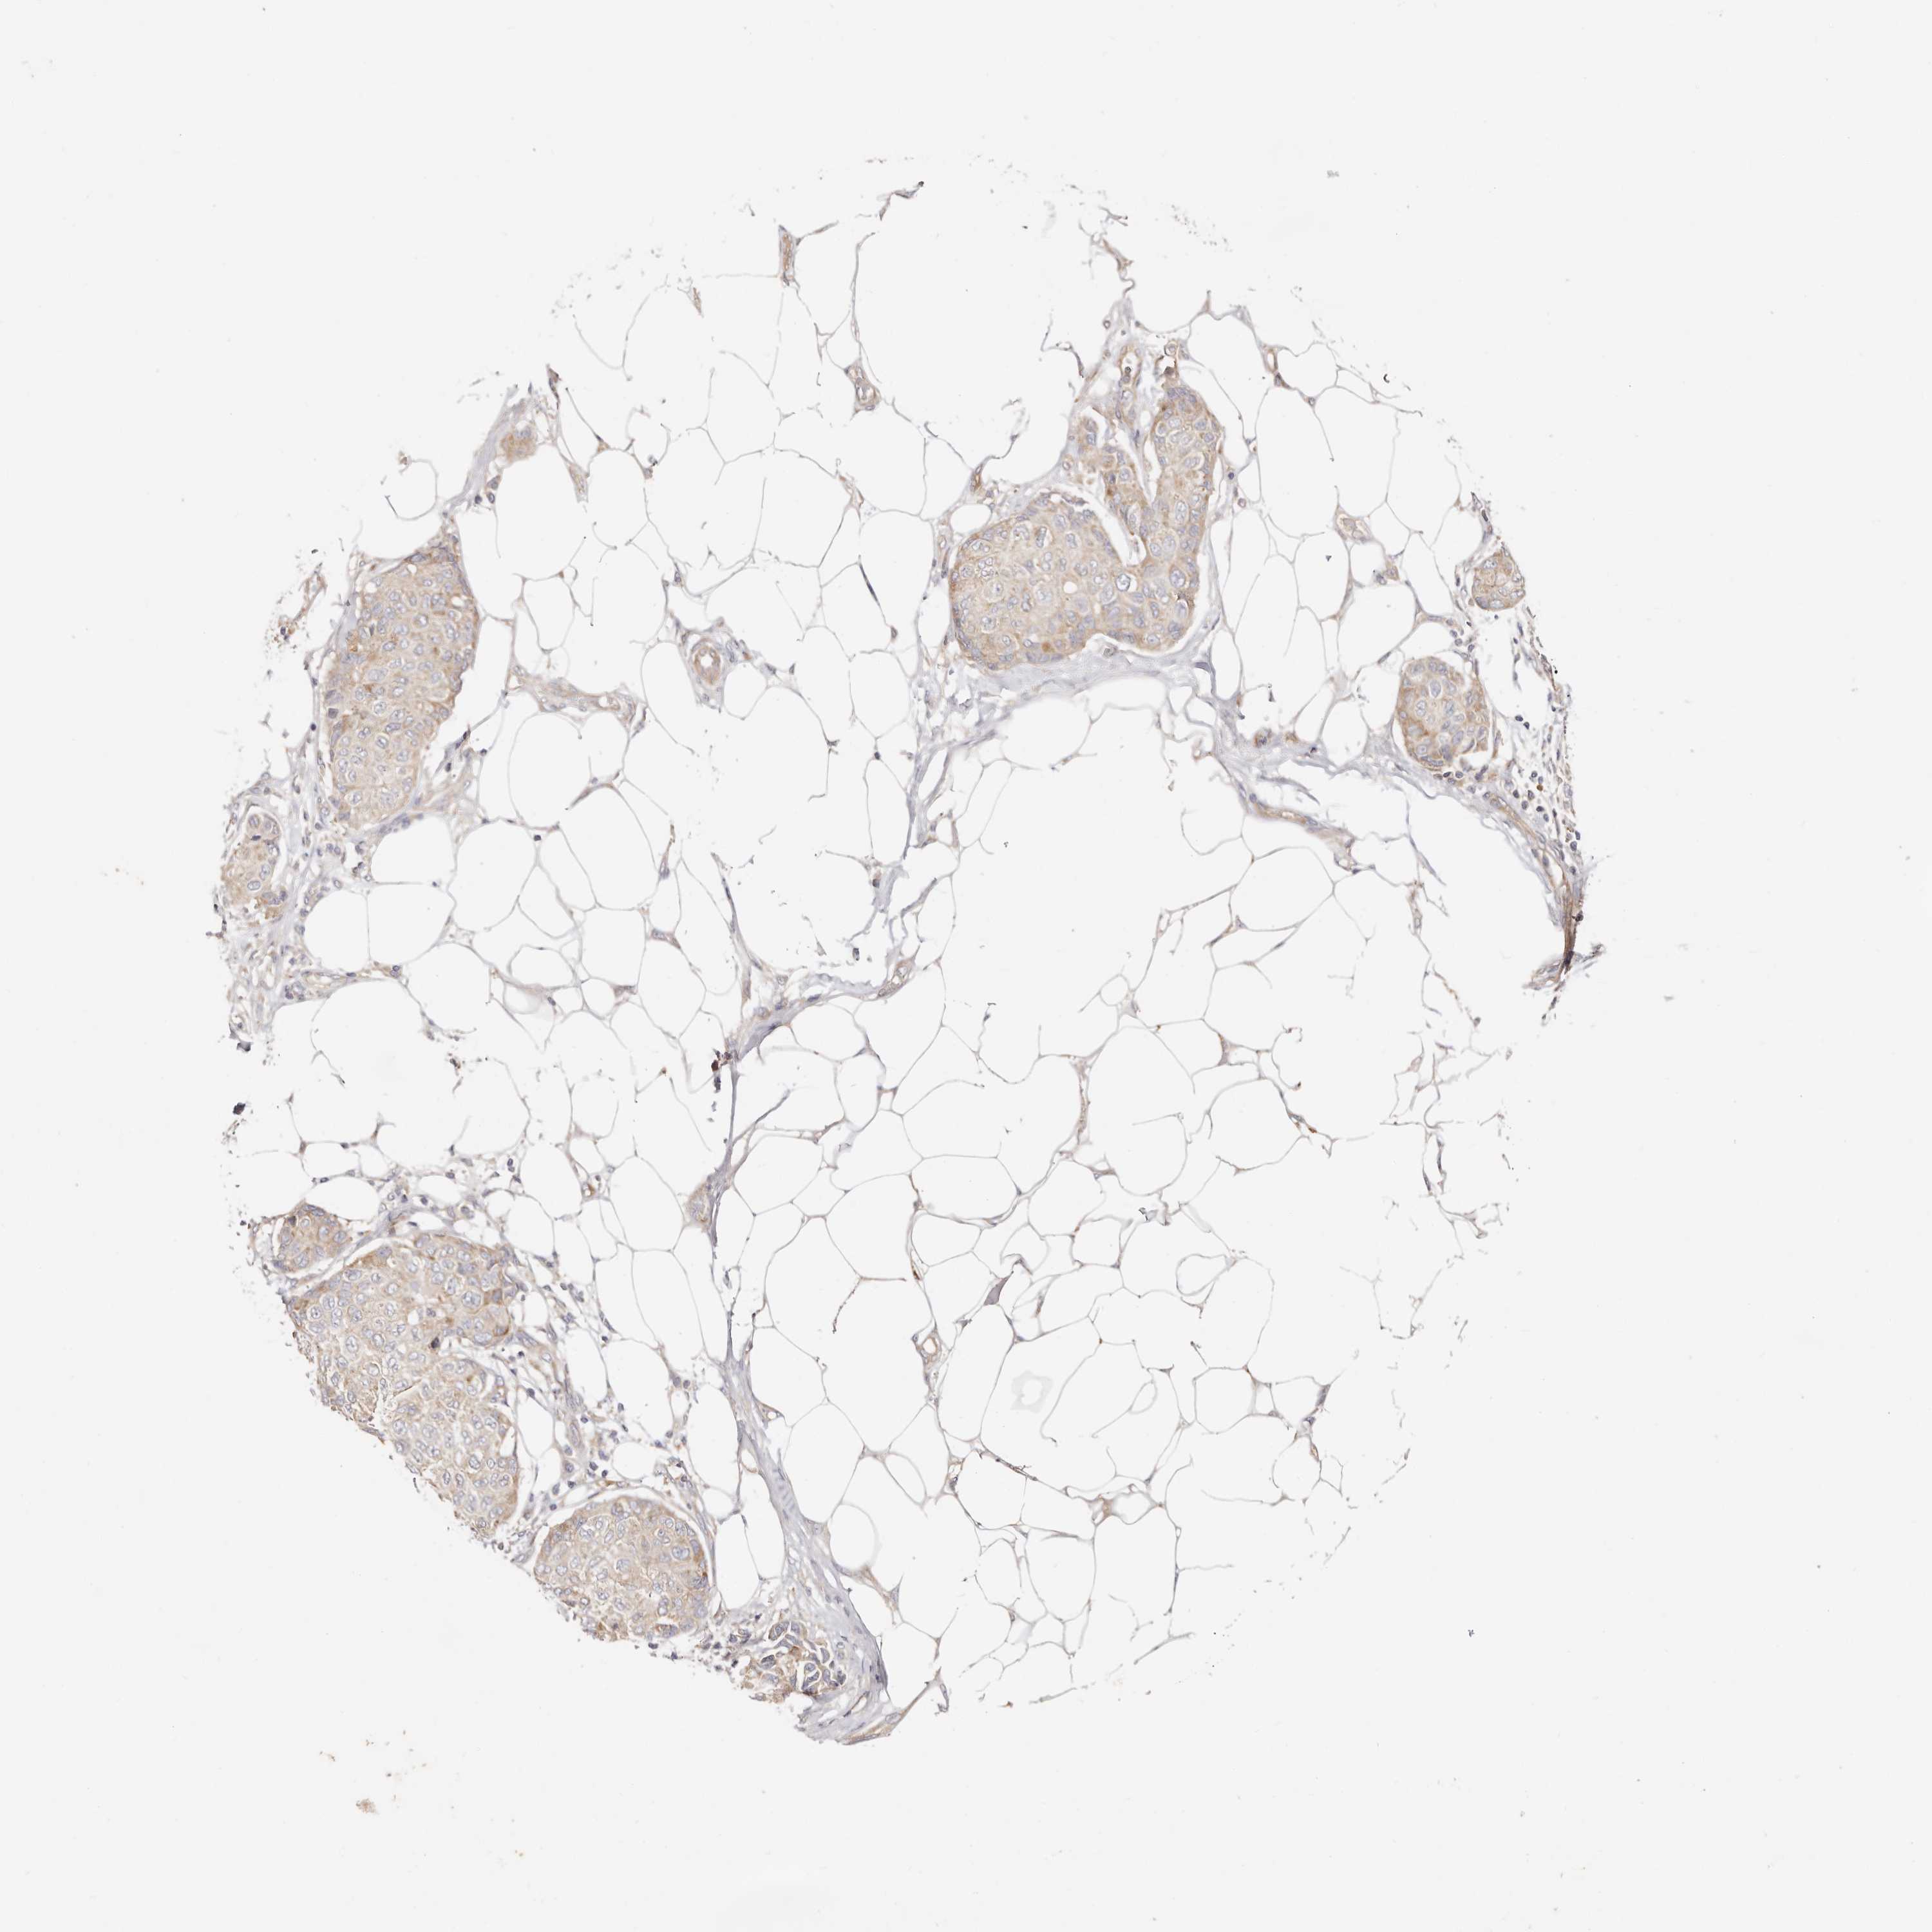

CANCER BREAST CANCER Show tissue menu

BRCA TCGA BRCA VALIDATION PROTEIN EXPRESSION